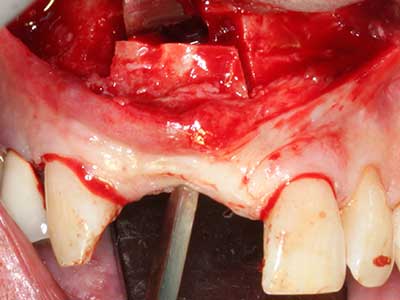

Автогенни костни присадки се използват под формата на блокчета, миди, пръстени и се комбинират с костозаместителни материали като стърготини. Ако имплантното ложе се обработва едновременно с аугментацията, различни системи за филтриране на кост са доказали своята ефективност за събиране на получените костни стърготини. В алтернатива, имплантното ложе може да бъде подготвено с апарат с ниски обороти без охлаждане. Ако не се постави имплант, костните стърготини от периферията могат да бъдат събрани с канюла за събиране на костен материал. Това също е възможно с пиезохирургия, използвайки специални накрайници, които събират костни стърготини с високо качество, в сравнение с костните стърготини, събрани с кръгли борери, както бе потвърдено в научно изследване, сравняващо двата метода (Chiriac, Herten et al. 2005).

Пиезохирургията има допълнителни предимства при събиране на костни блокове. В допълнение към високата прецизност при остеотомията, описана по-горе, употребата на фините режещи накрайници значително намаляват загубата на материал. Голяма загуба на материал по време на събиране може да се очаква с дебелите накрайници, особено при употреба на борери Линдеман (Lakshmiganthan, Gokulanathan et al. 2012). Базалното разделяне, което е необходимо, особено за присадка на блок при ретромолар, е улеснено от специално създадени правоъгълни триони. В резултат на това, пиезохирургията е разглеждана като прецизна, улеснена и безопасна процедура за събиране на костни блокове в ретромоларното пространство (Happe 2007) (Фиг. 1-12).